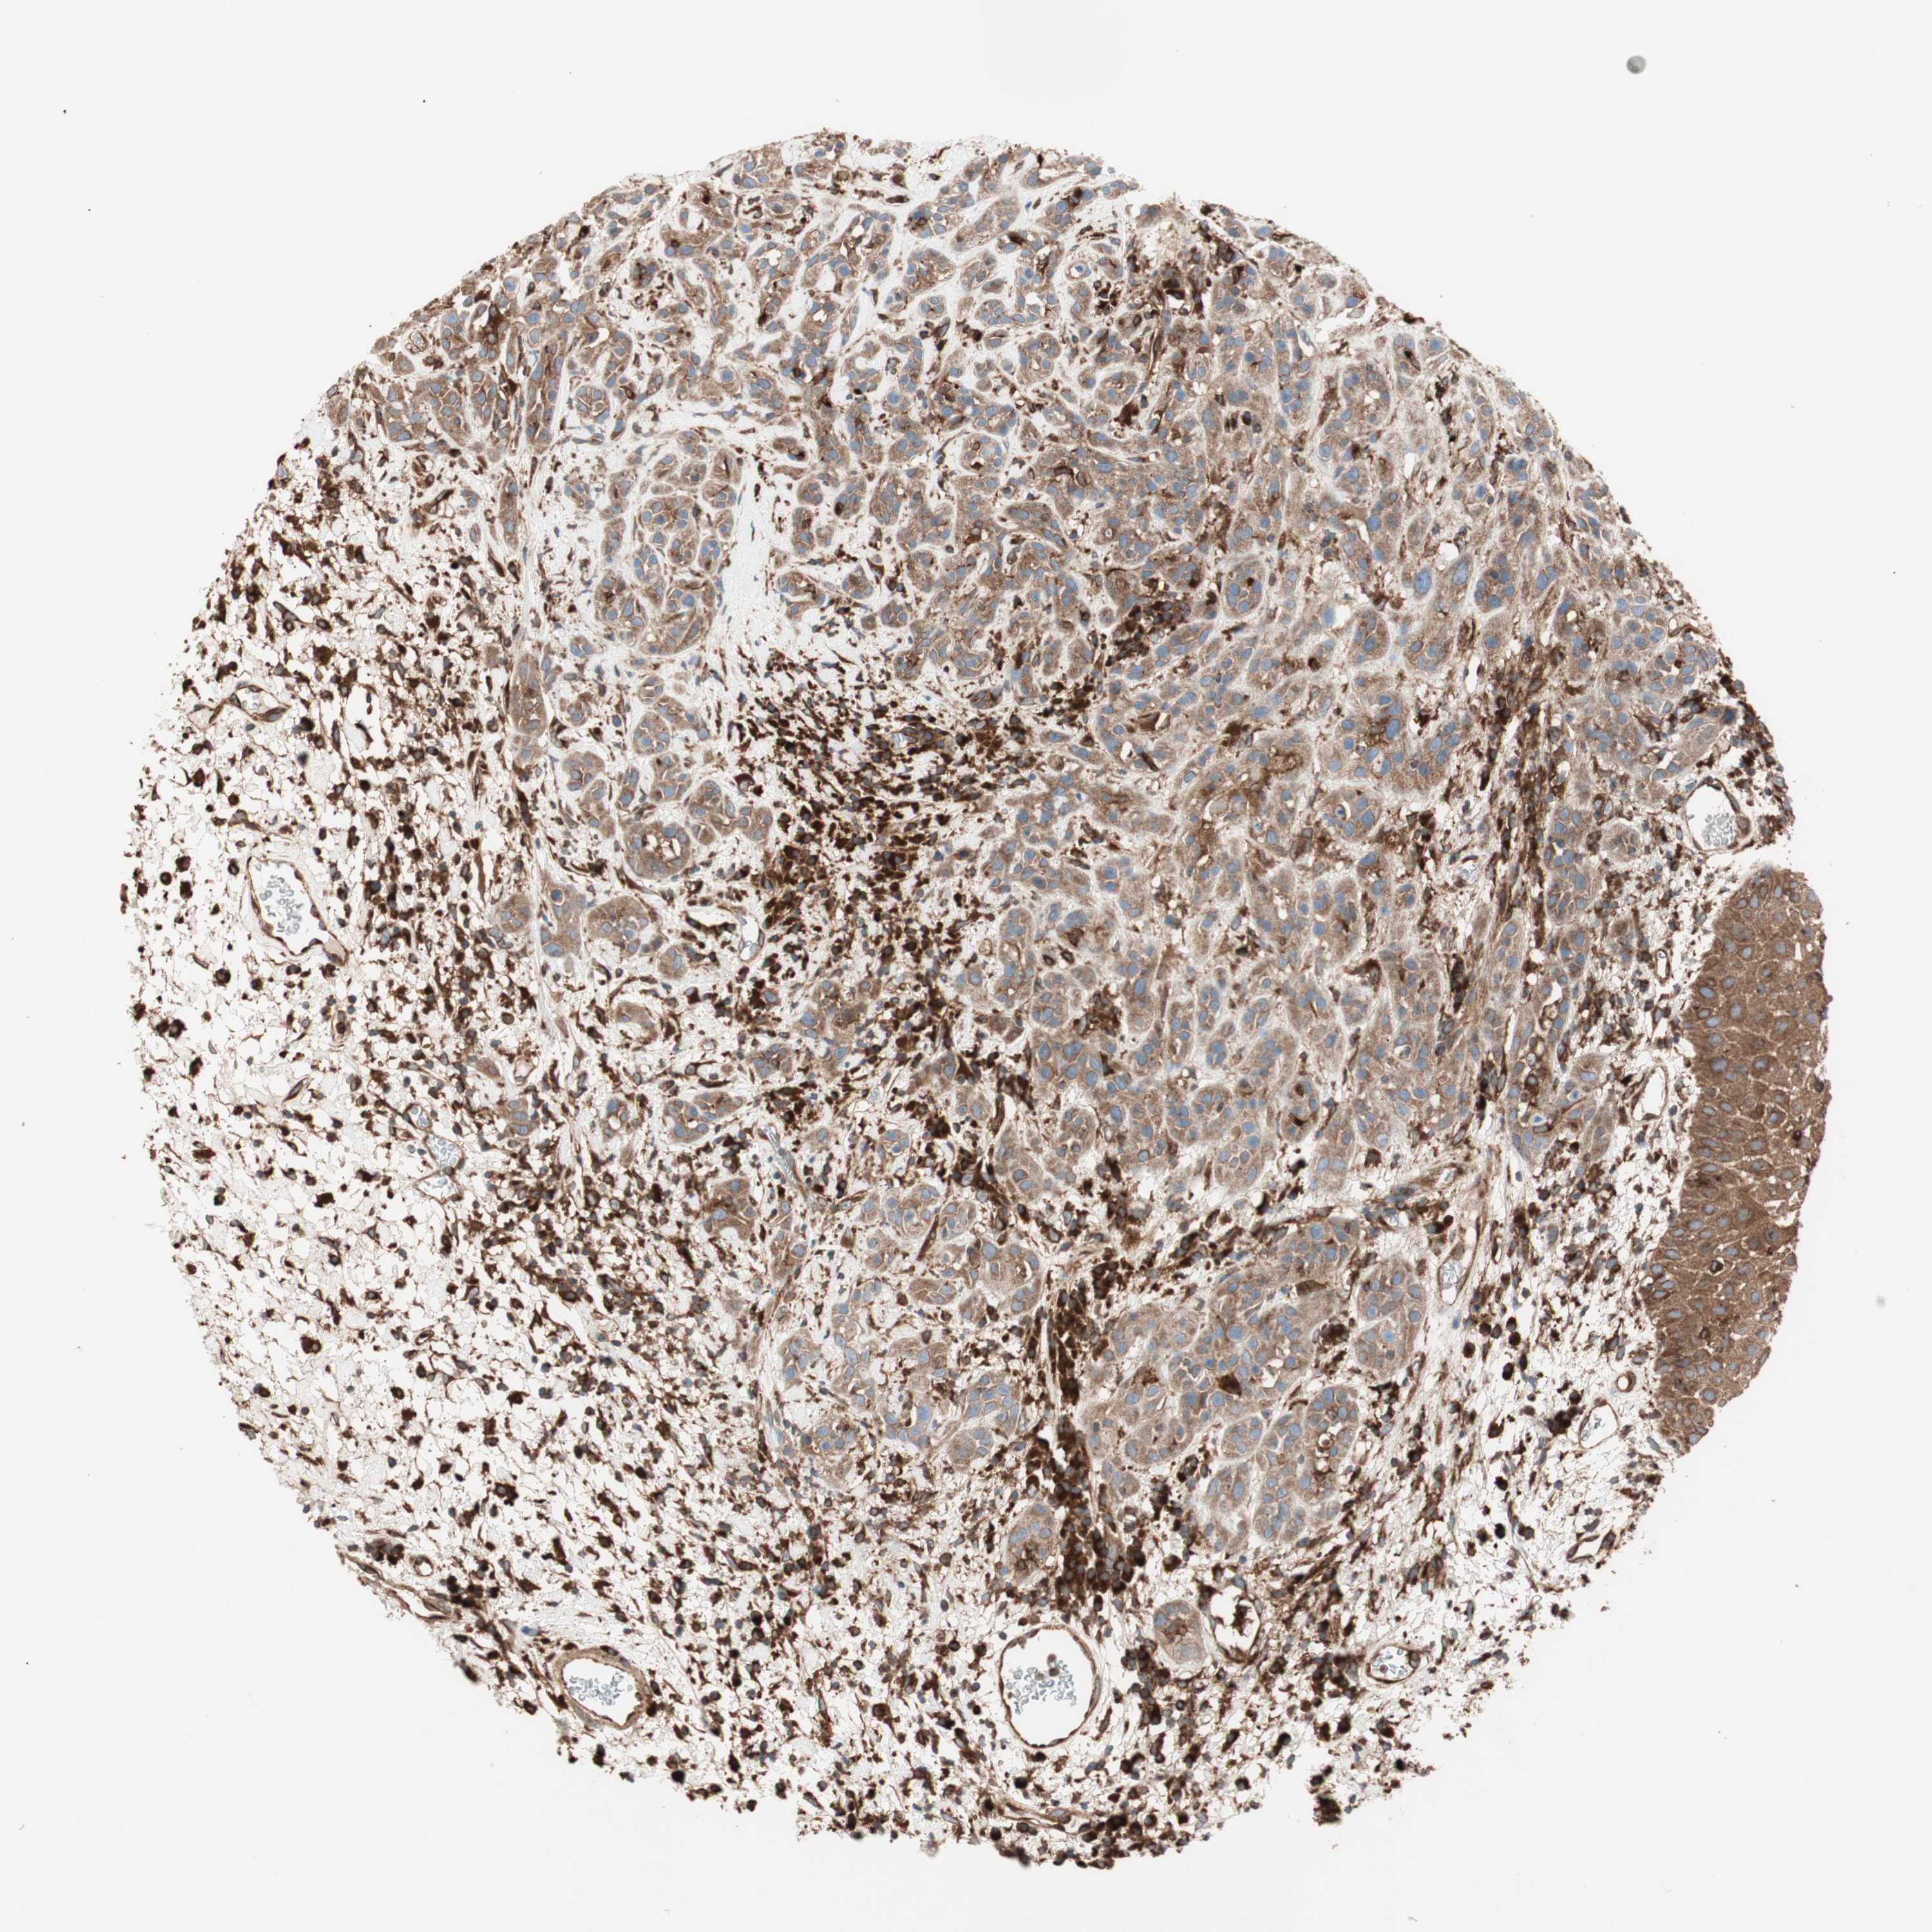

HEAD AND NECK CANCER - Protein expressioni

A mouse-over function shows sample information and annotation data. Click on an image to view it in a full screen mode. Samples can be filtered based on level of antibody staining by selecting one or several of the following categories: high, medium, low and not detected. The assay and annotation is described here.

Antibody stainingi

Antibody staining in the annotated cell types in the current human tissue is reported as not detected, low, medium, or high, based on conventional immunohistochemistry profiling in selected tissues. This score is based on the combination of the staining intensity and fraction of stained cells.

Each image is clickable and will lead to virtual microscopy that enables deeper exploration of all samples and also displays staining intensity scores, fraction scores and subcellular localization as well as patient and tissue information for each sample.

Antibody HPA049354

Antibody CAB004567

Staining

High

Medium

Low

Not detected

Intensity

Strong

Moderate

Weak

Negative

Quantity

>75%

75%-25%

<25%

None

Location

Nuclear

Cytoplasmic/membranous

Cytoplasmic/membranous,nuclear

Squamous cell carcinoma, NOS